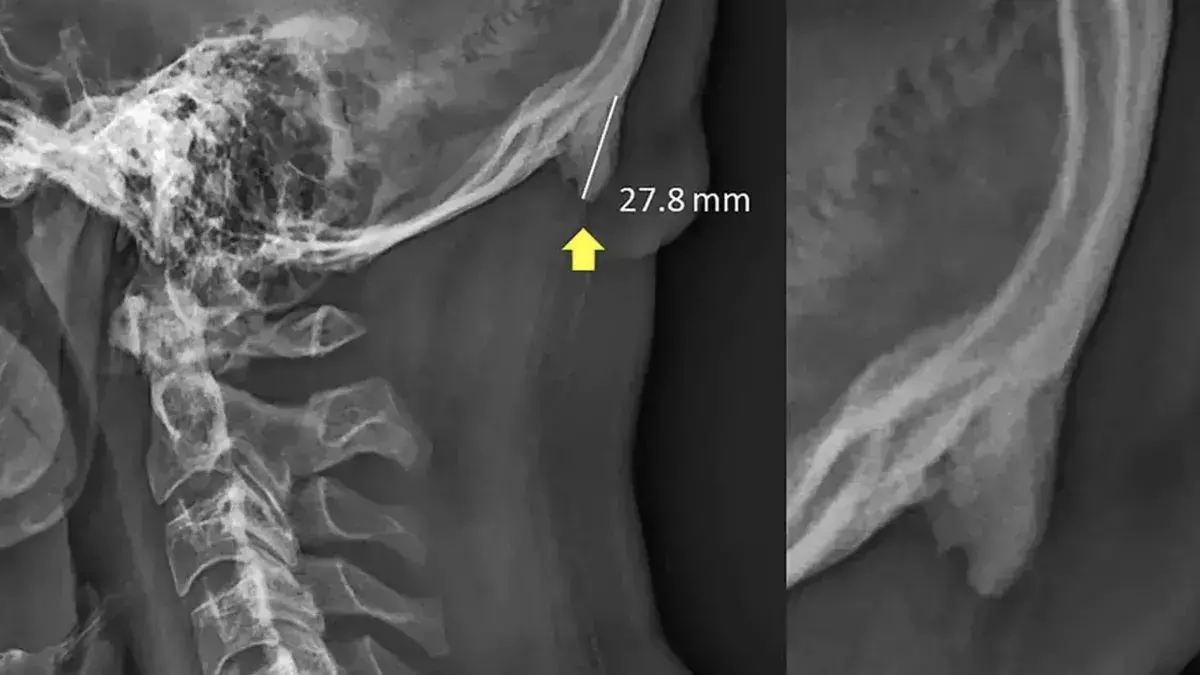

തലയോട്ടിക്ക് പുറകിലായി കഴുത്തിന് മുകളിലായിട്ടാണ് ഇത്തരമൊരു വളര്‍ച്ചകണ്ടെത്തിയത്. എക്‌സ്‌റേ കള്‍ പരിശോധിച്ചപ്പോഴാണ് ഇത് ഗവേഷകരുടെ ശ്രദ്ധയില്‍ പെട്ടത്. തുടര്‍ച്ചയായി സ്മാര്‍ട്ട്‌ഫോണോ സമാനമായ ഉപകരണങ്ങളോ നോക്കുന്നവരിലാണ് ഇത് കാണപ്പെടുന്നത്. തലതുടര്‍ച്ചയായി താഴ്ത്തിയിരിക്കുമ്പോള്‍ ഭാരം ക്രമീകരിക്കുന്നതിന്റെ ഭാഗമായാണ് ഈ ഭാഗത്ത് പ്രത്യേക വളര്‍ച്ച ഉണ്ടാകുന്നതെന്നാണ് ഗവേഷകരുടെ നിഗമനം.

2018 ഫെബ്രുവരിയില്‍ നാച്ചുര്‍ മാഗസിനില്‍ ഈ ഗവേഷണ പ്രബന്ധം പ്രസിദ്ധീകരിച്ചിരുന്നു. 18നും 86നും ഇടക്ക് പ്രായമുള്ളവരുടെ 1200 എക്‌സ്‌റേകളാണ് ഗവേഷകര്‍ പഠനത്തിനായി ഉപയോഗിച്ചത്. 33 ശതമാനം പേര്‍ക്കും ഇത്തരത്തില്‍ തലയോട്ടിക്ക് താഴെയായി വളര്‍ച്ച കാണപ്പെട്ടു. പ്രായം കൂടുംതോറും ഈ വളര്‍ച്ച കുറയുന്നുവെന്നും പ്രബന്ധം പറയുന്നു. അതേസമയം ഈ പ്രബന്ധത്തിലെ സൂചനകളും നിഗമനങ്ങലും മാത്രം കണക്കിലെടുത്ത് സ്മാര്‍ട്ട്‌ഫോണിനെ മാത്രം കുറ്റക്കാരായി കണക്കാക്കാനാവില്ലെന്ന വിമര്‍ശനവും ഉയരുന്നുണ്ട്.